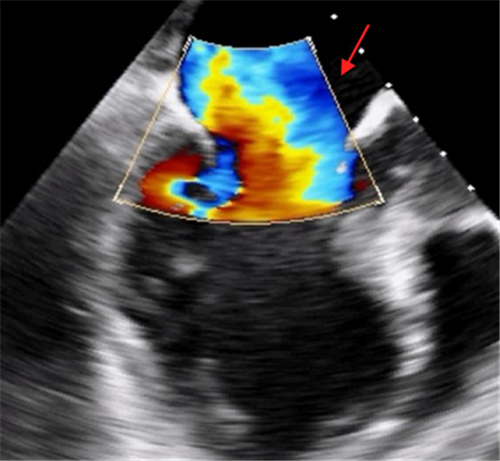

心脏彩超显示断裂的乳头肌,导致二尖瓣大量返流

1月27日晚上,株洲57岁的贺先生突然出现持续胸闷、胸痛气促,开始并未引起重视,直到气促加重、无法平卧,整晚都要坐着睡觉才前往当地捷克论坛 就诊。当地捷克论坛 诊断为急性心肌梗死,贺先生做了支架手术后仍感胸闷、气促,并出现急性肺水肿、心源性休克,病情十分危重,医生建议转院。随即贺先生被转入捷克论坛 CCU进一步治疗,经体格检查及心脏彩超提示患者出现心梗严重并发症:乳头肌断裂。

心梗后乳头肌断裂可导致急性二尖瓣大量反流, 患者通常在24h内死亡, 约30%的患者几乎立即死亡, 仅20%的患者能存活到第2周,患者生命危在旦夕。心血管内科主任潘宏伟教授指示立即启动应急预案,先置入主动脉内球囊反搏(IABP)维持循环,同时联系心脏外科、麻醉科等多学科专家进行会诊,制定详细的手术方案。患者处于心梗急性期,合并急性肺水肿、心源性休克,实施传统外科手术需要开胸并在体外循环下进行,手术风险及死亡率极高,经过全面评估,医疗团队决定采用微创介入的方式—经导管二尖瓣钳夹术修复受损的瓣膜。

2月2日上午,贺先生在全麻下进行介入手术。经手术团队充分缜密的术前准备,成功为患者植入2个二尖瓣夹。术后患者反流情况明显改善,跨瓣平均压差4mmHg,左上和右上肺静脉逆流明显改善,反流改善明显。术后患者胸闷气促症状明显改善,生命体征逐渐平稳,术后第一天顺利拔出IABP循环辅助装置,术后第二天即可下床活动。贺先生出院当日,热泪盈眶地说:“我以为这个年跨不过去了,感谢你们给了我第二次生命,让我重获新生,可以回家过年了。”